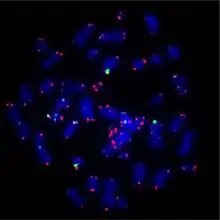

HCT116 is a human colon cancer cell line used in therapeutic research and drug screenings.[1]

HCT116 cells have a mutation in codon 13 of the KRAS proto-oncogene, and are suitable transfection targets for gene therapy research.[2] The cells have an epithelial morphology and can metastasize in xenograft models.[1] When transducted with viral vectors carrying the p53 gene, HCT116 cells remain arrested in the G1 phase.[3] The proliferation of HCT116 colonies was found to be inhibited by 5-Fu/P85 copolymer micelles.[4] Furthermore, it was found that the knockout of MARCH2 limited growth of HCT116 cells via stress on the endoplasmic reticulum.[5]